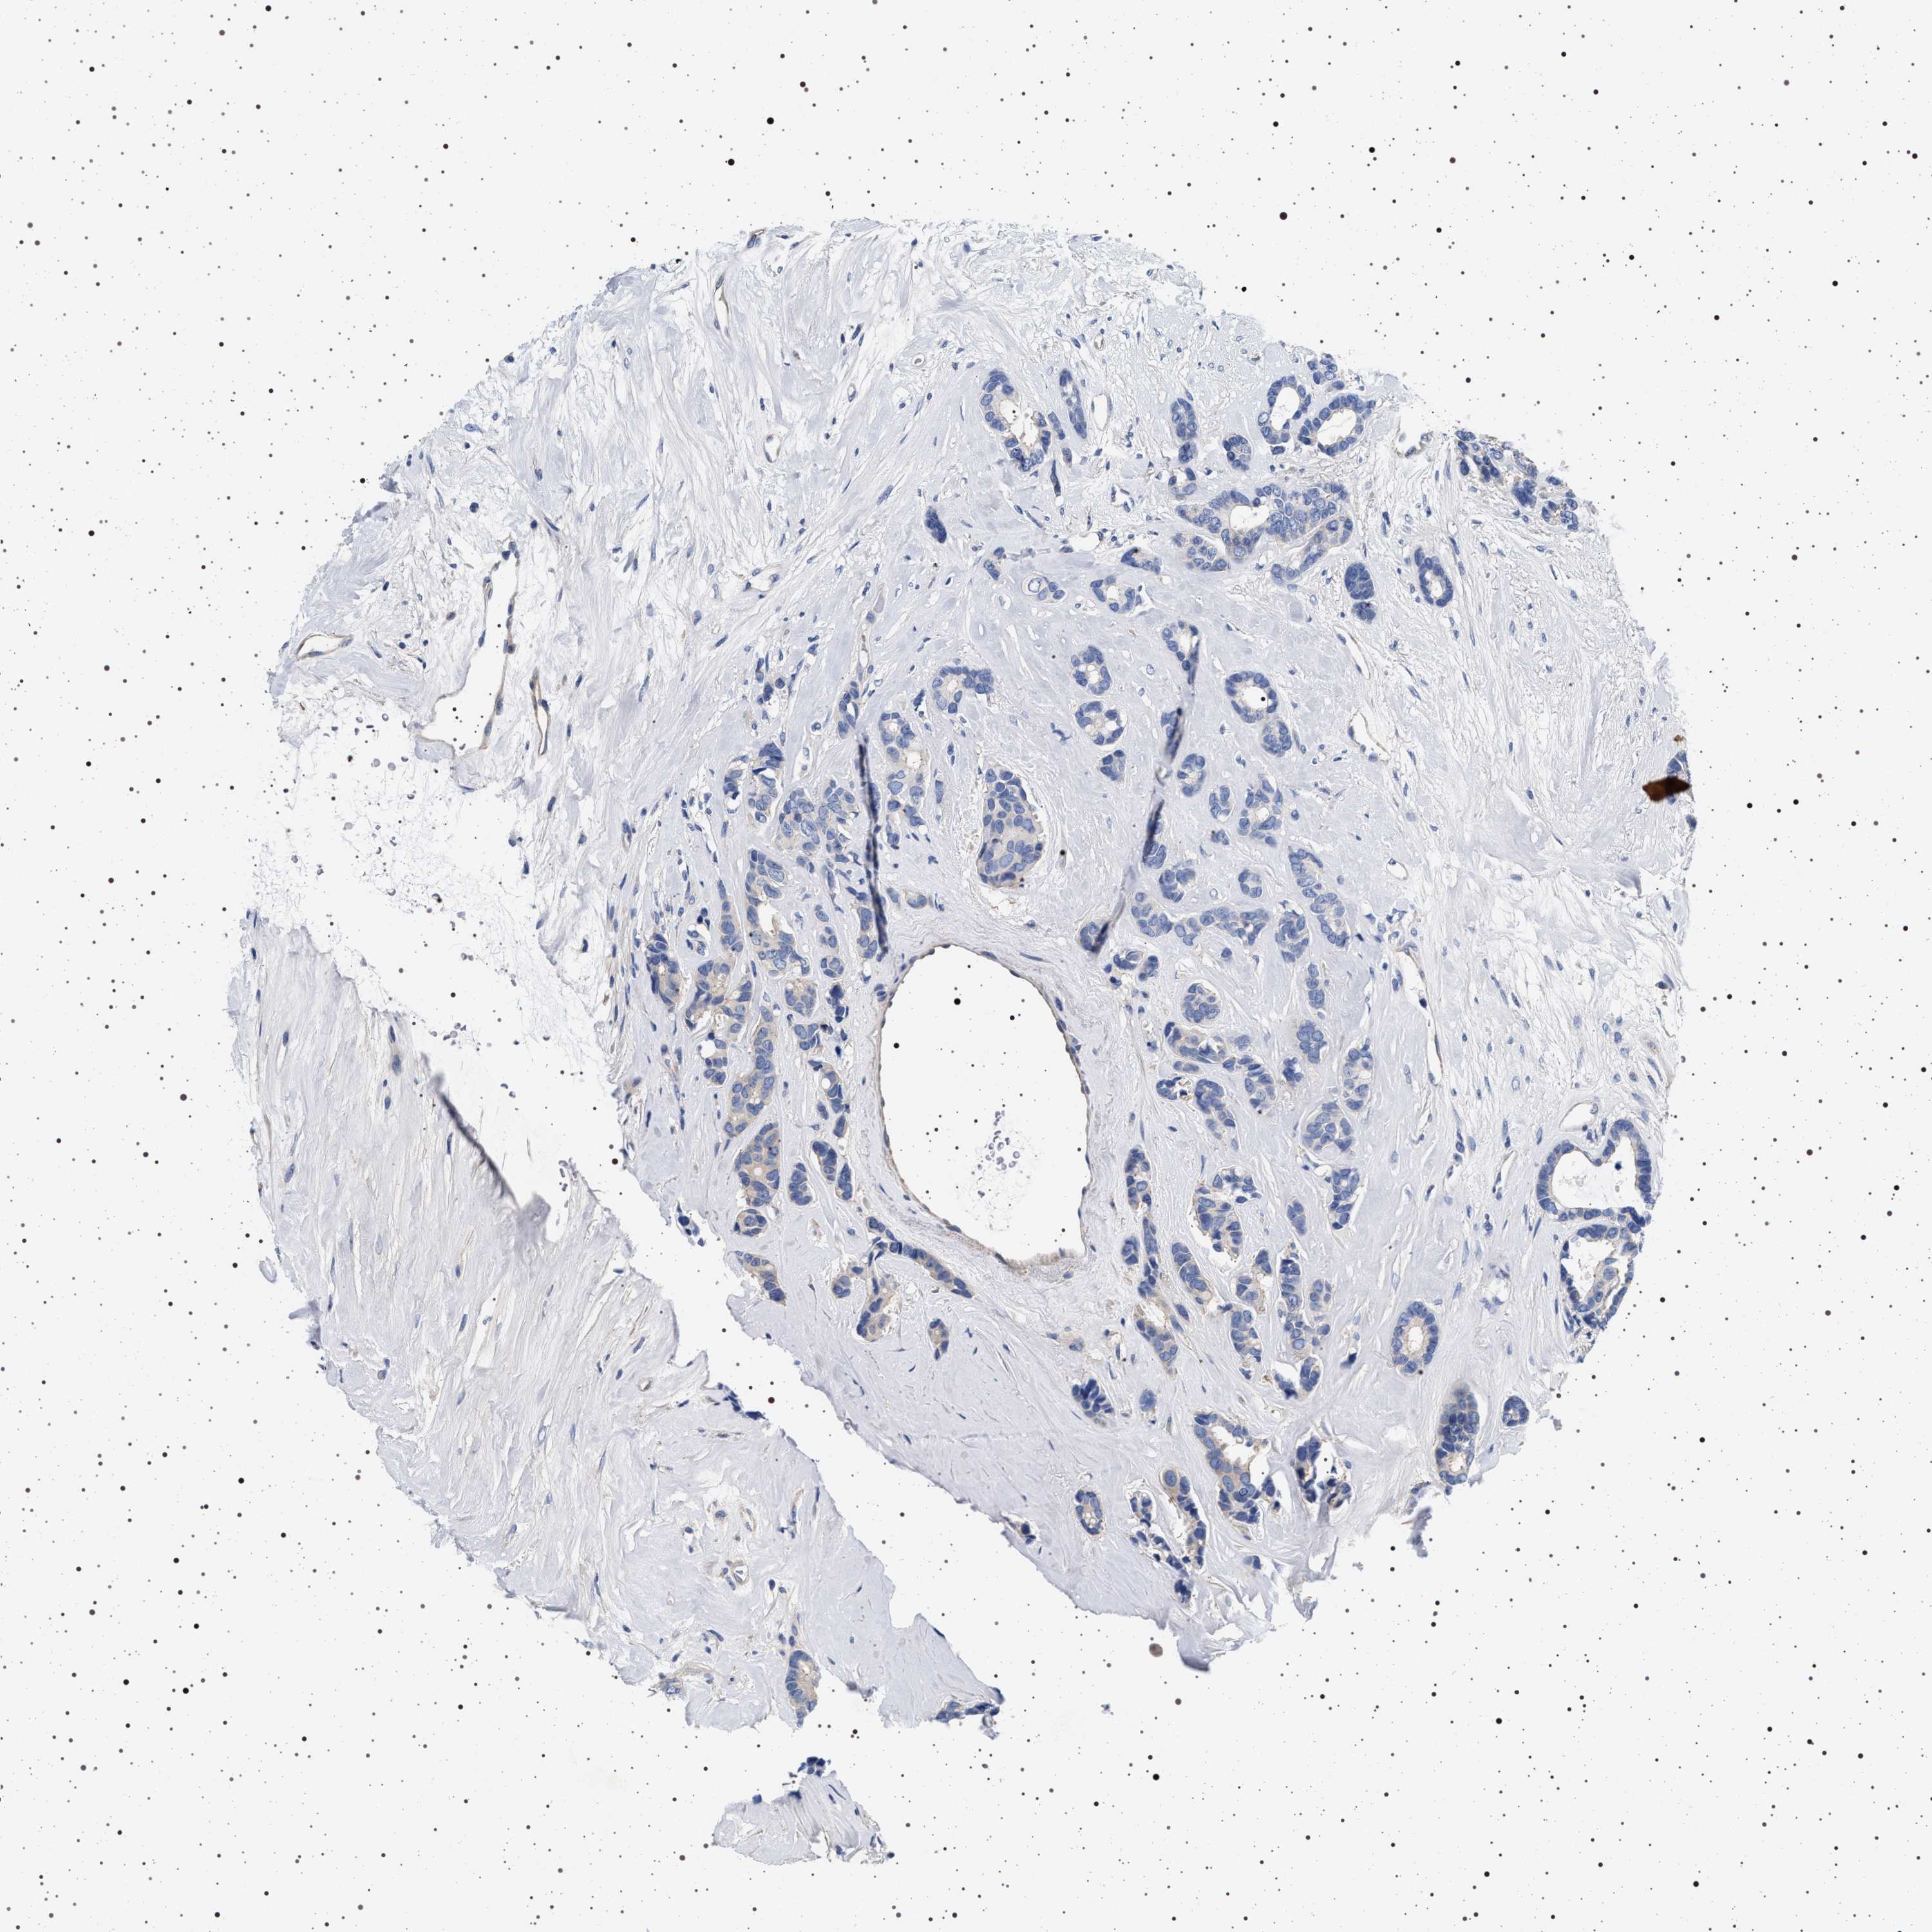

CANCER BREAST CANCER Show tissue menu

BRCA TCGA BRCA VALIDATION PROTEIN EXPRESSION